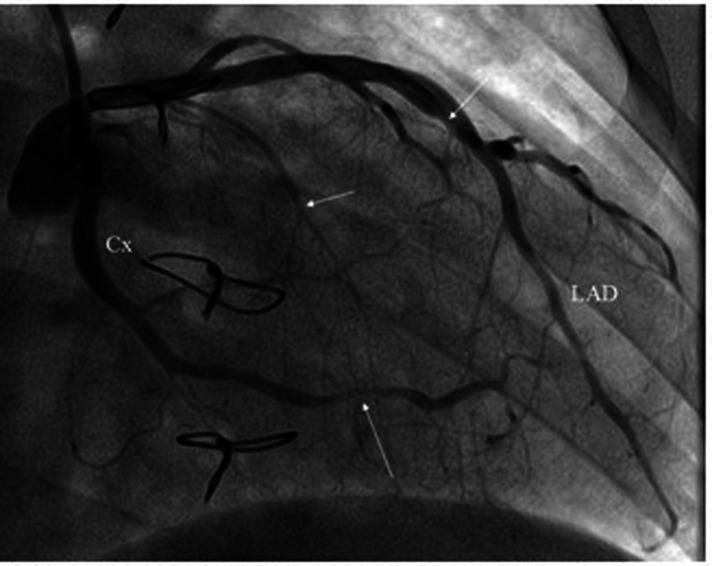

Heart transplant recipients undergo extensive invasive and non-invasive postoperative screening to exclude complications, such as allograft rejection and vasculopathy. Cardiac magnetic resonance imaging is a non-invasive, non-irradiating, diagnostic tool for monitoring graft health and identifying possible tissue rejection or myocardial fibrosis. We describe the case of a 29-year-old female heart transplant recipient admitted to our care center with a worsening clinical condition. The patient underwent clinical evaluation, blood tests, including troponin I and N-terminal pro brain type natriuretic peptide, transthoracic echocardiography, invasive coronary angiography, and cardiovascular magnetic resonance imaging. Cardiovascular magnetic resonance imaging showed widespread sub-epicardial hyperintensity of the myocardial segments along the course of the coronary arteries. T2 mapping sequences showed an elevated value and the myocardial native T1 values and extracellular volume percentage were significantly increased. Late gadolinium enhancement demonstrated a diffuse sub-epicardial hypersignal along the lateral, free, and left ventricular walls. All the sequences evidenced widespread hyper-enhancement of epicardial fat along the course of the thickened main coronary artery walls. One month later, the recipient underwent re-transplantation due to progressive worsening of the clinical condition and refractoriness to intravenous medication. The anatomopathological findings of the explanted heart provided impressive visualization of structural and histopathological changes. These results could guide the tailoring of preventive therapeutic strategies and non-invasive monitoring of cardiac grafts.